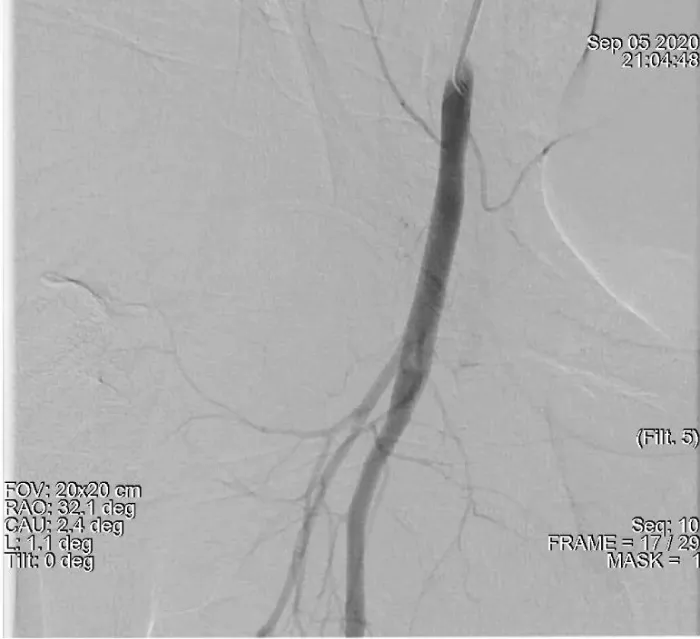

Figure 2: Demonstrates a large amount of extravascular contrast with the right iliac angiogram location near the middle third of the femoral head. suggestive of active bleeding from mid right common femoral artery into the pelvis.

The case presented here can be considered as a case of RPH resulting from normal lower site puncture of common femoral artery as contrast leakage on angiography is at the level of the middle 1/3 of the femoral head only (Figure 5). Here RPH can be due to multiple puncture (two leakage points can be seen on angiography) and can be explained by direct superior connection of the anatomical femoral sheath with the retroperitoneum leading to RPH [3]. The other risk factor could be a low BSA which was 1.61 meter².

Figure 5: Demonstrates a large amount of extravascular contrast with the right iliac angiogram location at the level of middle third of the femoral head with two leakage points. suggestive of active bleeding from mid right common femoral artery into the pelvis.